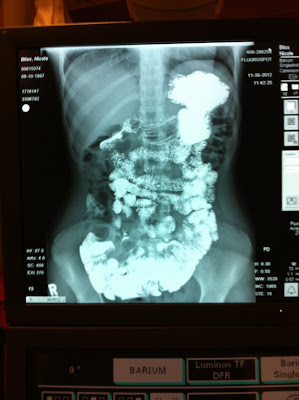

Another test :( !!!!!!

The tests continues and with each test we rule out something. But we also continue to wonder and wait for an answer !!!!